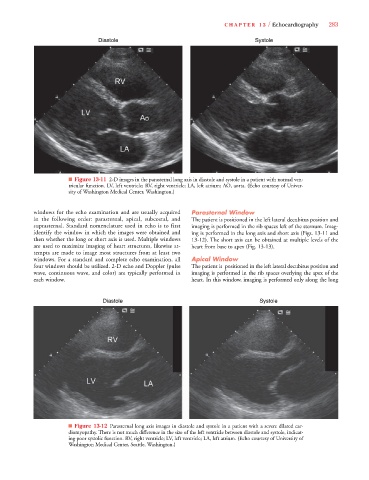

Diastole Systole

■ Figure 13-11 2-D images in the parasternal long axis in diastole and systole in a patient with normal ven-

tricular function. LV, left ventricle; RV, right ventricle; LA, left atrium; AO, aorta. (Echo courtesy of Univer-

sity of Washington Medical Center, Washington.)

■ Figure 13-12 Parasternal long axis images in diastole and systole in a patient with a severe dilated car-

diomyopathy. There is not much difference in the size of the left ventricle between diastole and systole, indicat-

ing poor systolic function. RV, right ventricle; LV, left ventricle; LA, left atrium. (Echo courtesy of University of

Washington Medical Center, Seattle, Washington.)